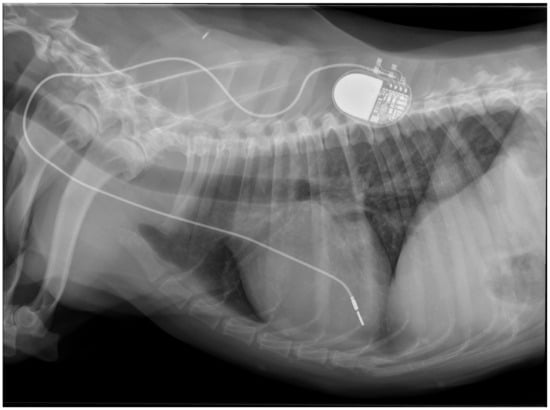

Physical examination at the authors’ institution, three years after the pacemaker implantation, revealed a bright, alert and responsive dog with a respiratory rate of 60 breaths/min and a pulse rate of 44 beats/min. The rectal temperature was 39.5 °C. The dog had received the last dose of antibiotics a day previously. Thoracic radiographs, an electrocardiogram, an echocardiogram, an abdominal ultrasound examination, urinalysis, and feces and blood tests were performed in order to identify the cause of the cough, hyperthermia and bradycardia. Thoracic radiographs showed no abnormalities and the position of the pacemaker lead was identical to that of the radiographs performed immediately after implantation (Figure 2). Electrocardiography showed a good functioning pacemaker, and ventricular premature complexes with periods of ventricular tachycardia (Figure 3 and Figure 4), which were assumed to have caused the pulse deficit.

Figure 2.

Thoracic radiographs of a dog with chronic cough, hyperthermia and increased respiratory rate show no pulmonary pathology and unchanged position of the pacemaker electrode compared to the direct post-operative radiographs.